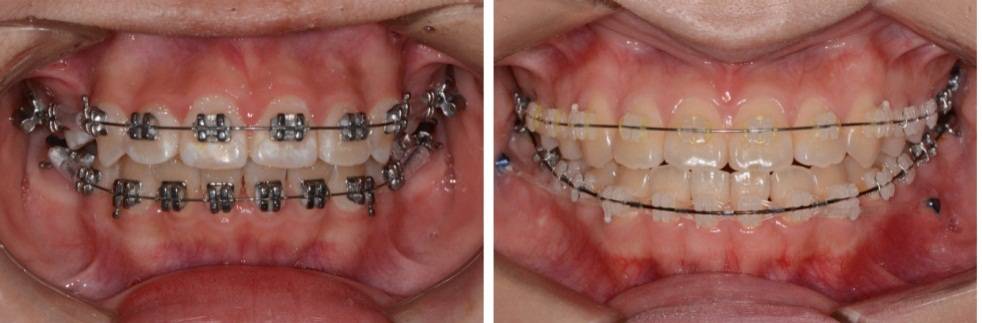

正 畸-正颌联合治疗矫治不对称牙颌面畸形

对于错牙合畸形的治疗,最常见的方式是正畸治疗。而对于一些严重的骨性畸形例如反牙合(地包天)、不对称牙颌面畸形等,则需进行正畸与正颌手术的联合治疗。